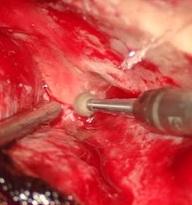

Intracerebral hemorrhage of basal ganglia, surgical management through transinsular transylvian approach. case report

GIUSEPPE ROJAS P.1a, JESÚS FLORES Q.2b